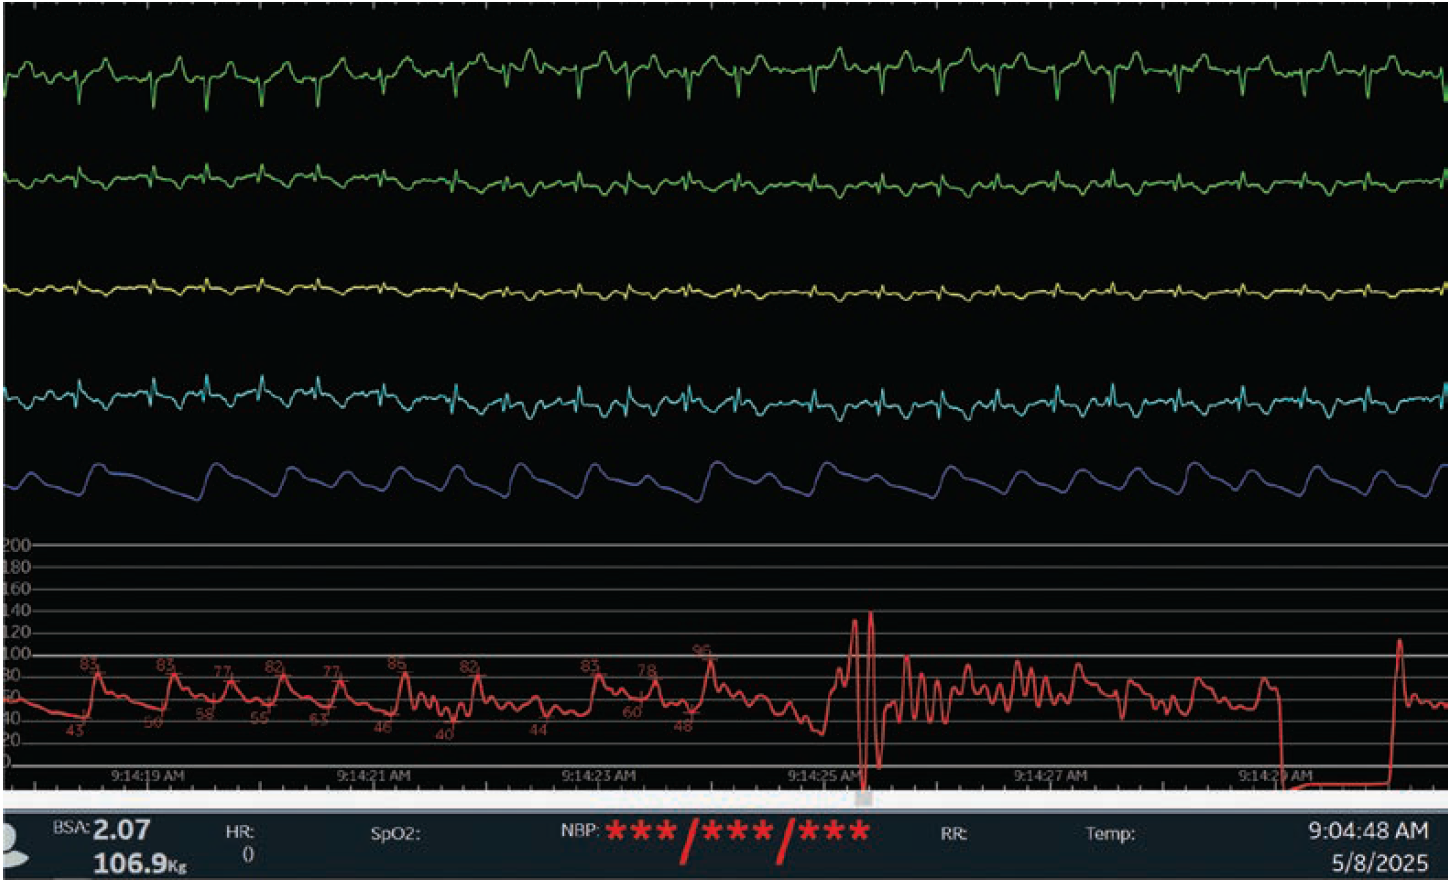

Shortly thereafter, the patient developed worsening hypotension (blood pressure 60/40 mmHg) and transient ST-segment elevation (STE) in the anterior leads (Figures 1-2) was noted. At no time did the patient have chest pain. Emergent fluid resuscitation and atropine (1.0 mg) were administered for the presumed vagal reaction. Coronary angiography was repeated to treat vasospasm if causative, but no spasm was present. Within minutes after restoration of the blood pressure (95/78 mmHg), the patient’s ST-segment elevations resolved spontaneously and returned to baseline (Figure 3).

We were surprised to see the STE come and go with the level of hypotension. No evidence of obstructive coronary artery disease, coronary dissection, or vasospasm could be found. The left and right coronary arteries were widely patent with no visible thrombus or spasm.